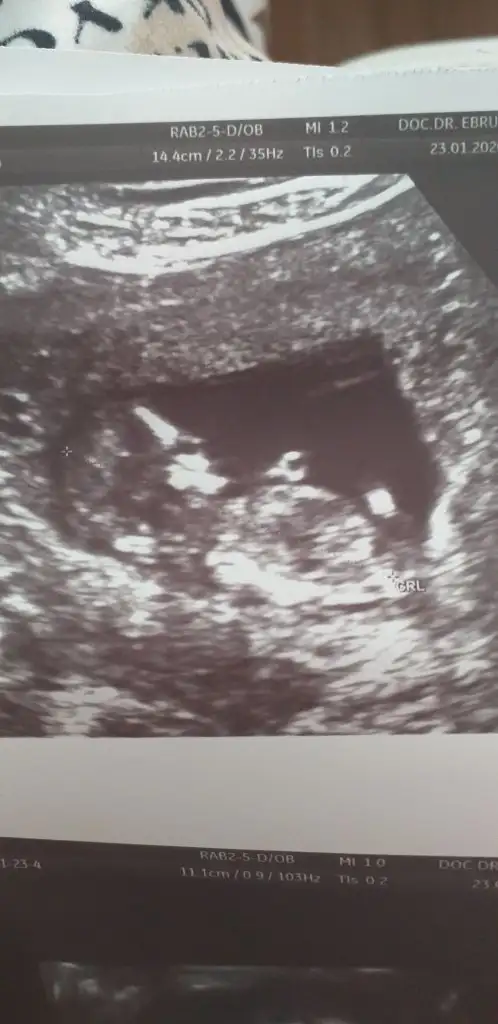

Benimkinide değerlendirebilir misiniz ?? Kız mı erkek mi

Eklentiler

• 690363EB-1215-4855-A5FA-F7339D1FD8F5.webp

690363EB-1215-4855-A5FA-F7339D1FD8F5.webp

17,7 KB · Görüntüleme: 34